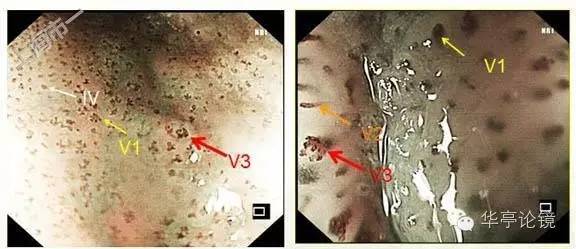

ME--NBI内镜:IPCL为IV、V1型为主,散在少许局灶见V2、V3型改变,预测病变深度为m1为主。

ME-NBI内镜:病灶区未见分支血管网,IPCL形态异常,分布不均,走形紊乱,局部有缺失,呈V2-V3型改变。(注:V3型:不规则并伴有血管袢结构的部分破坏)。